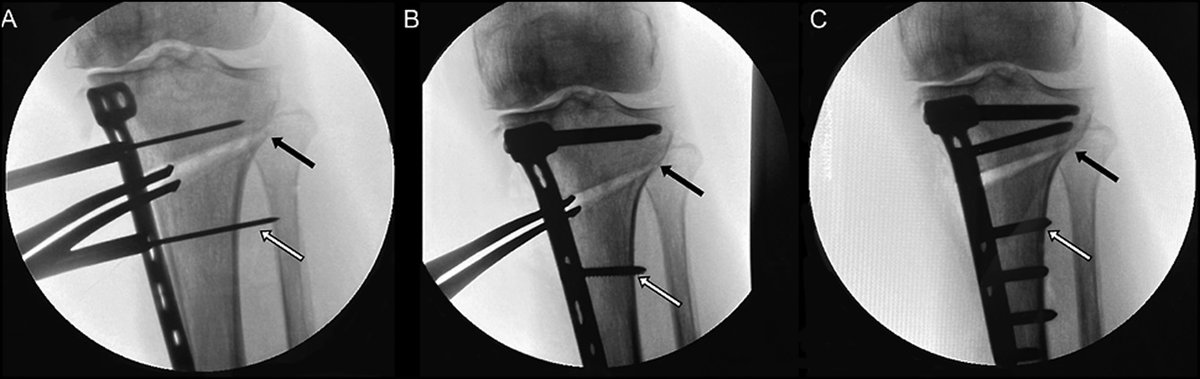

Case of septic non union distal tibia with reaction of infection and acute shortening and proximal lengthening osteotomy, pt develped procurvatum deformity due unstable ring , acute correction done of regenerate,notice the hinge position.